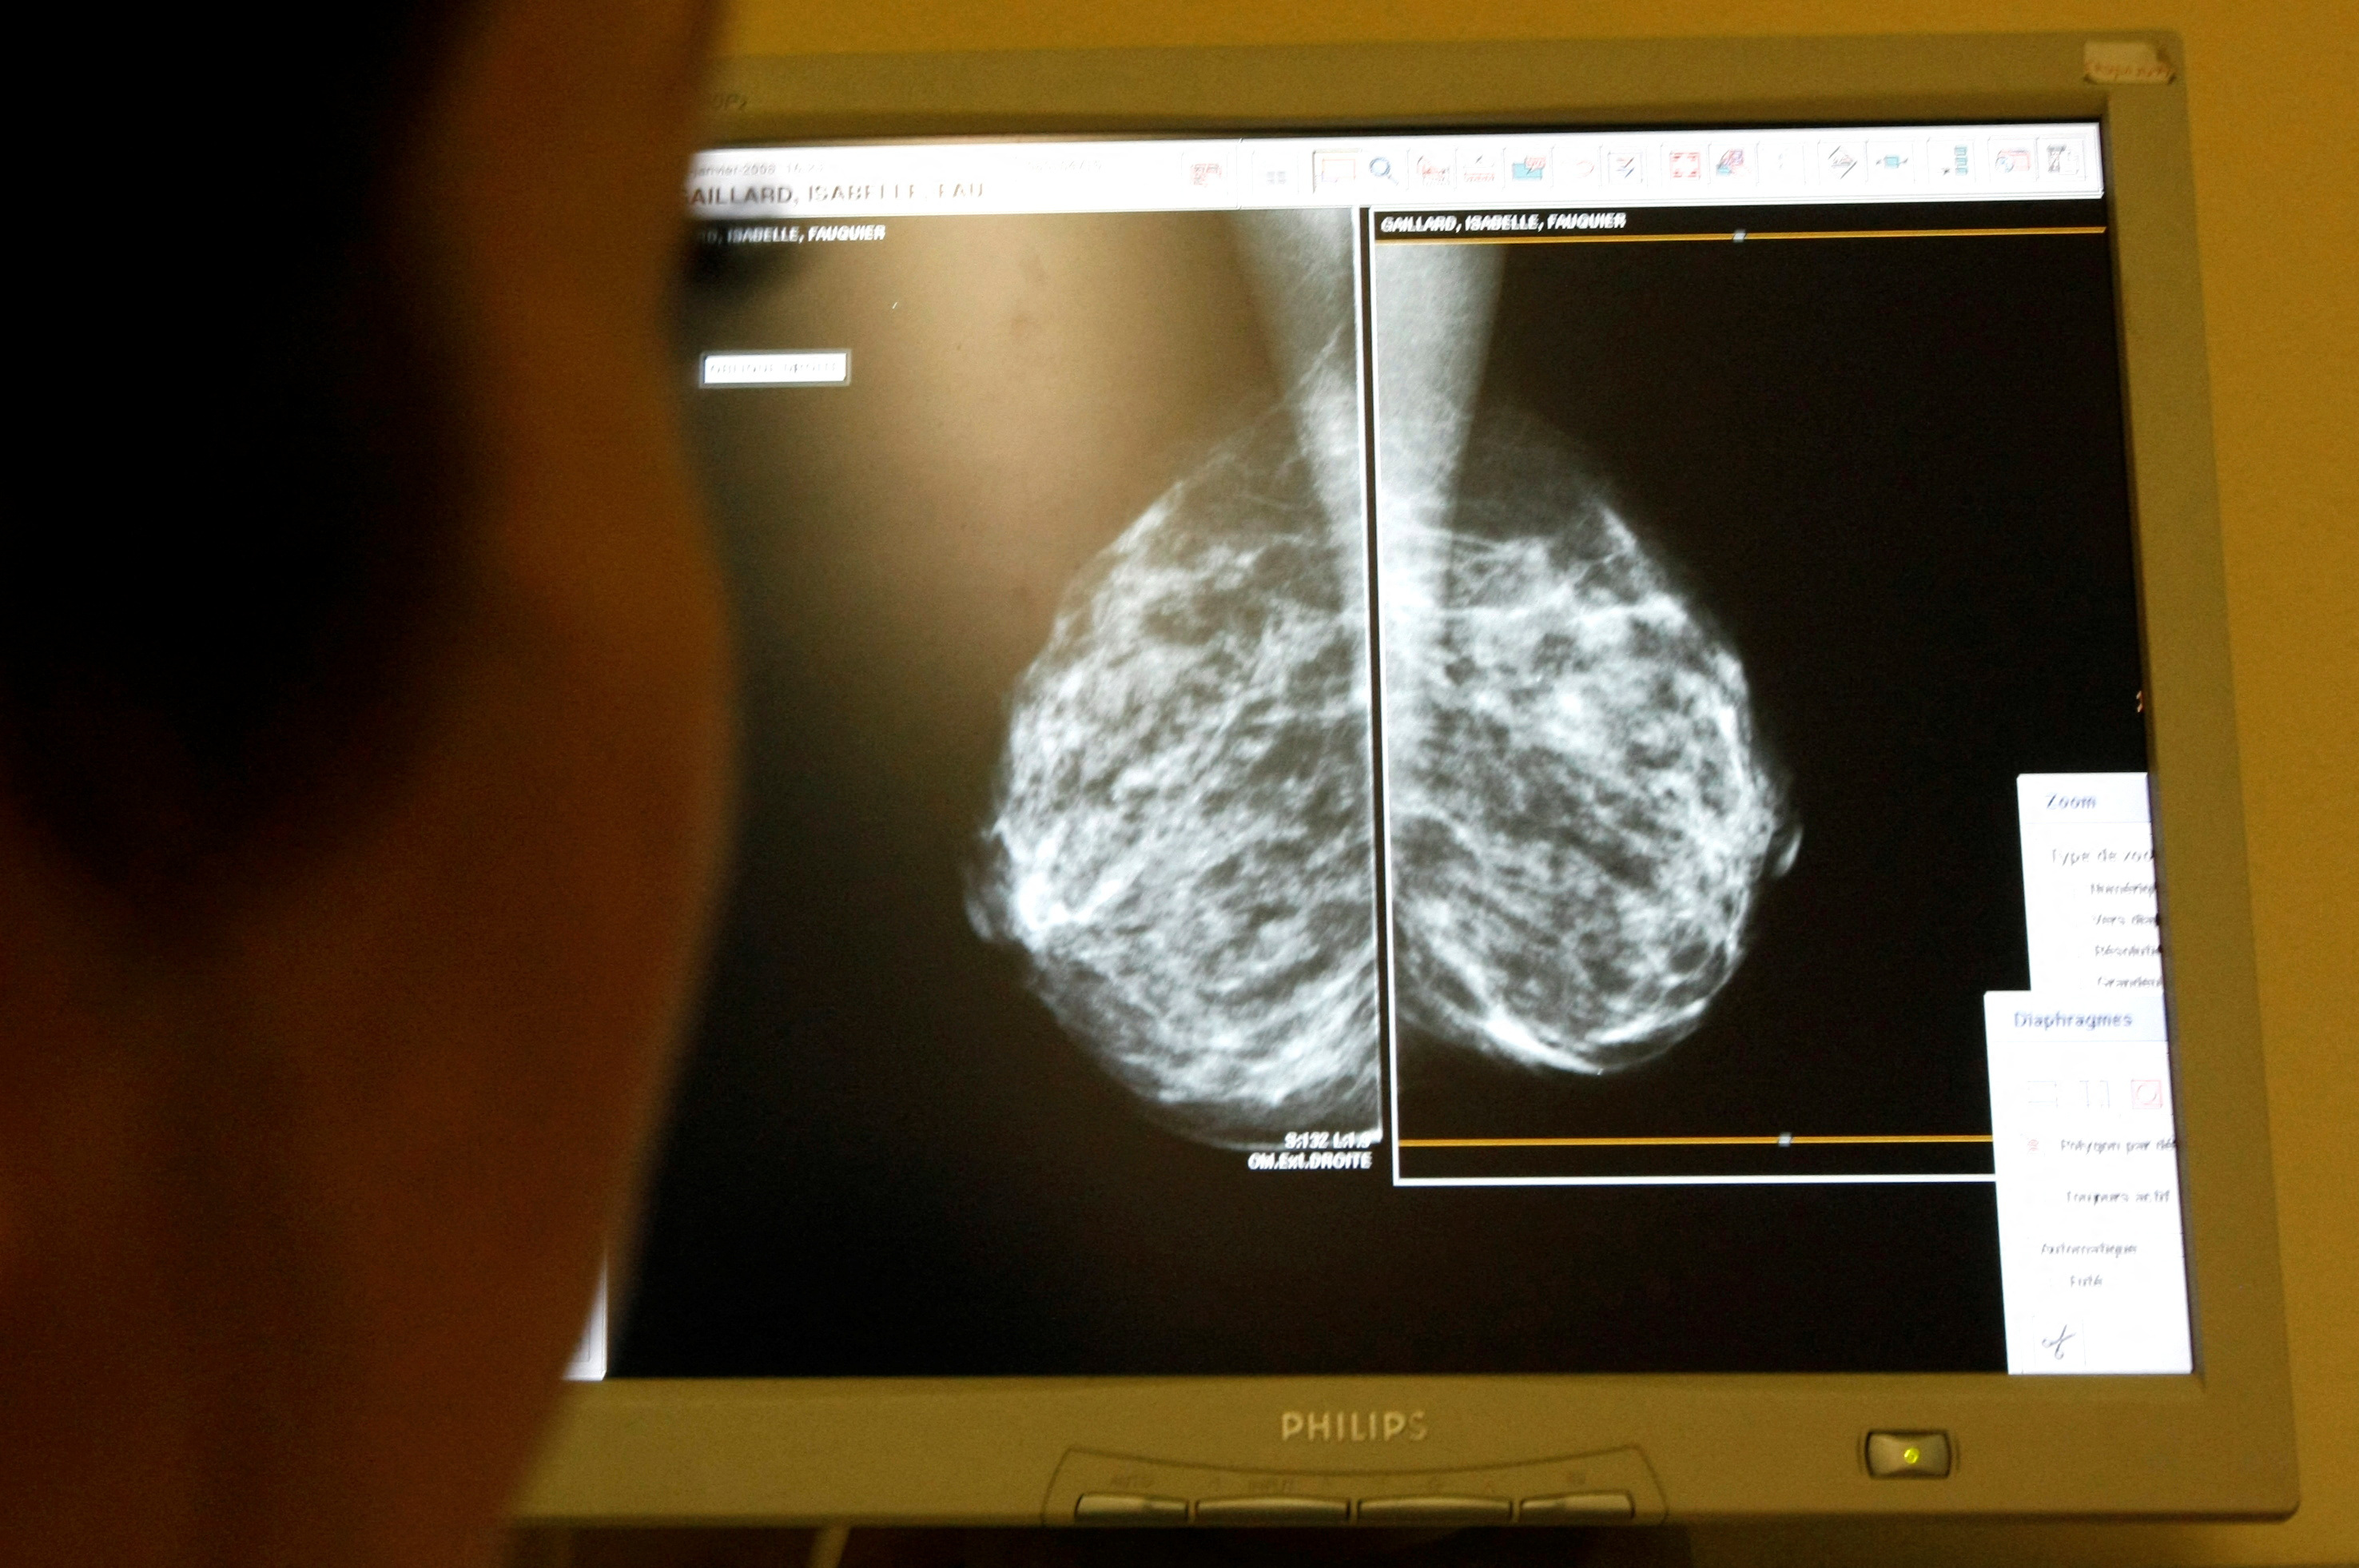

US panel advises breast cancer screenings should begin at age 40

Lowering age for biennial screenings could result in more lives being saved, US health task force says.

Women should begin getting mammogram screenings for breast cancer at age 40, an influential United States health panel has advised, in a move the US Preventive Services Task Force (USPSTF) said could help save thousands of lives.